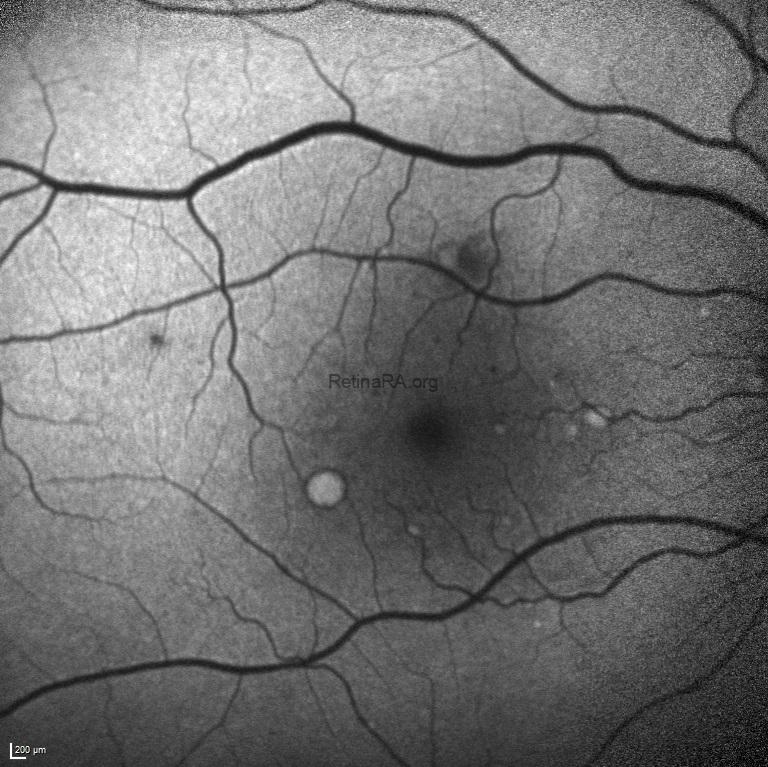

Fundus autofluorescence imaging exhibited the hyper-autofluorescence of drusen and hypo-autoflurescence of retinal microaneurysms and hemorrhages.